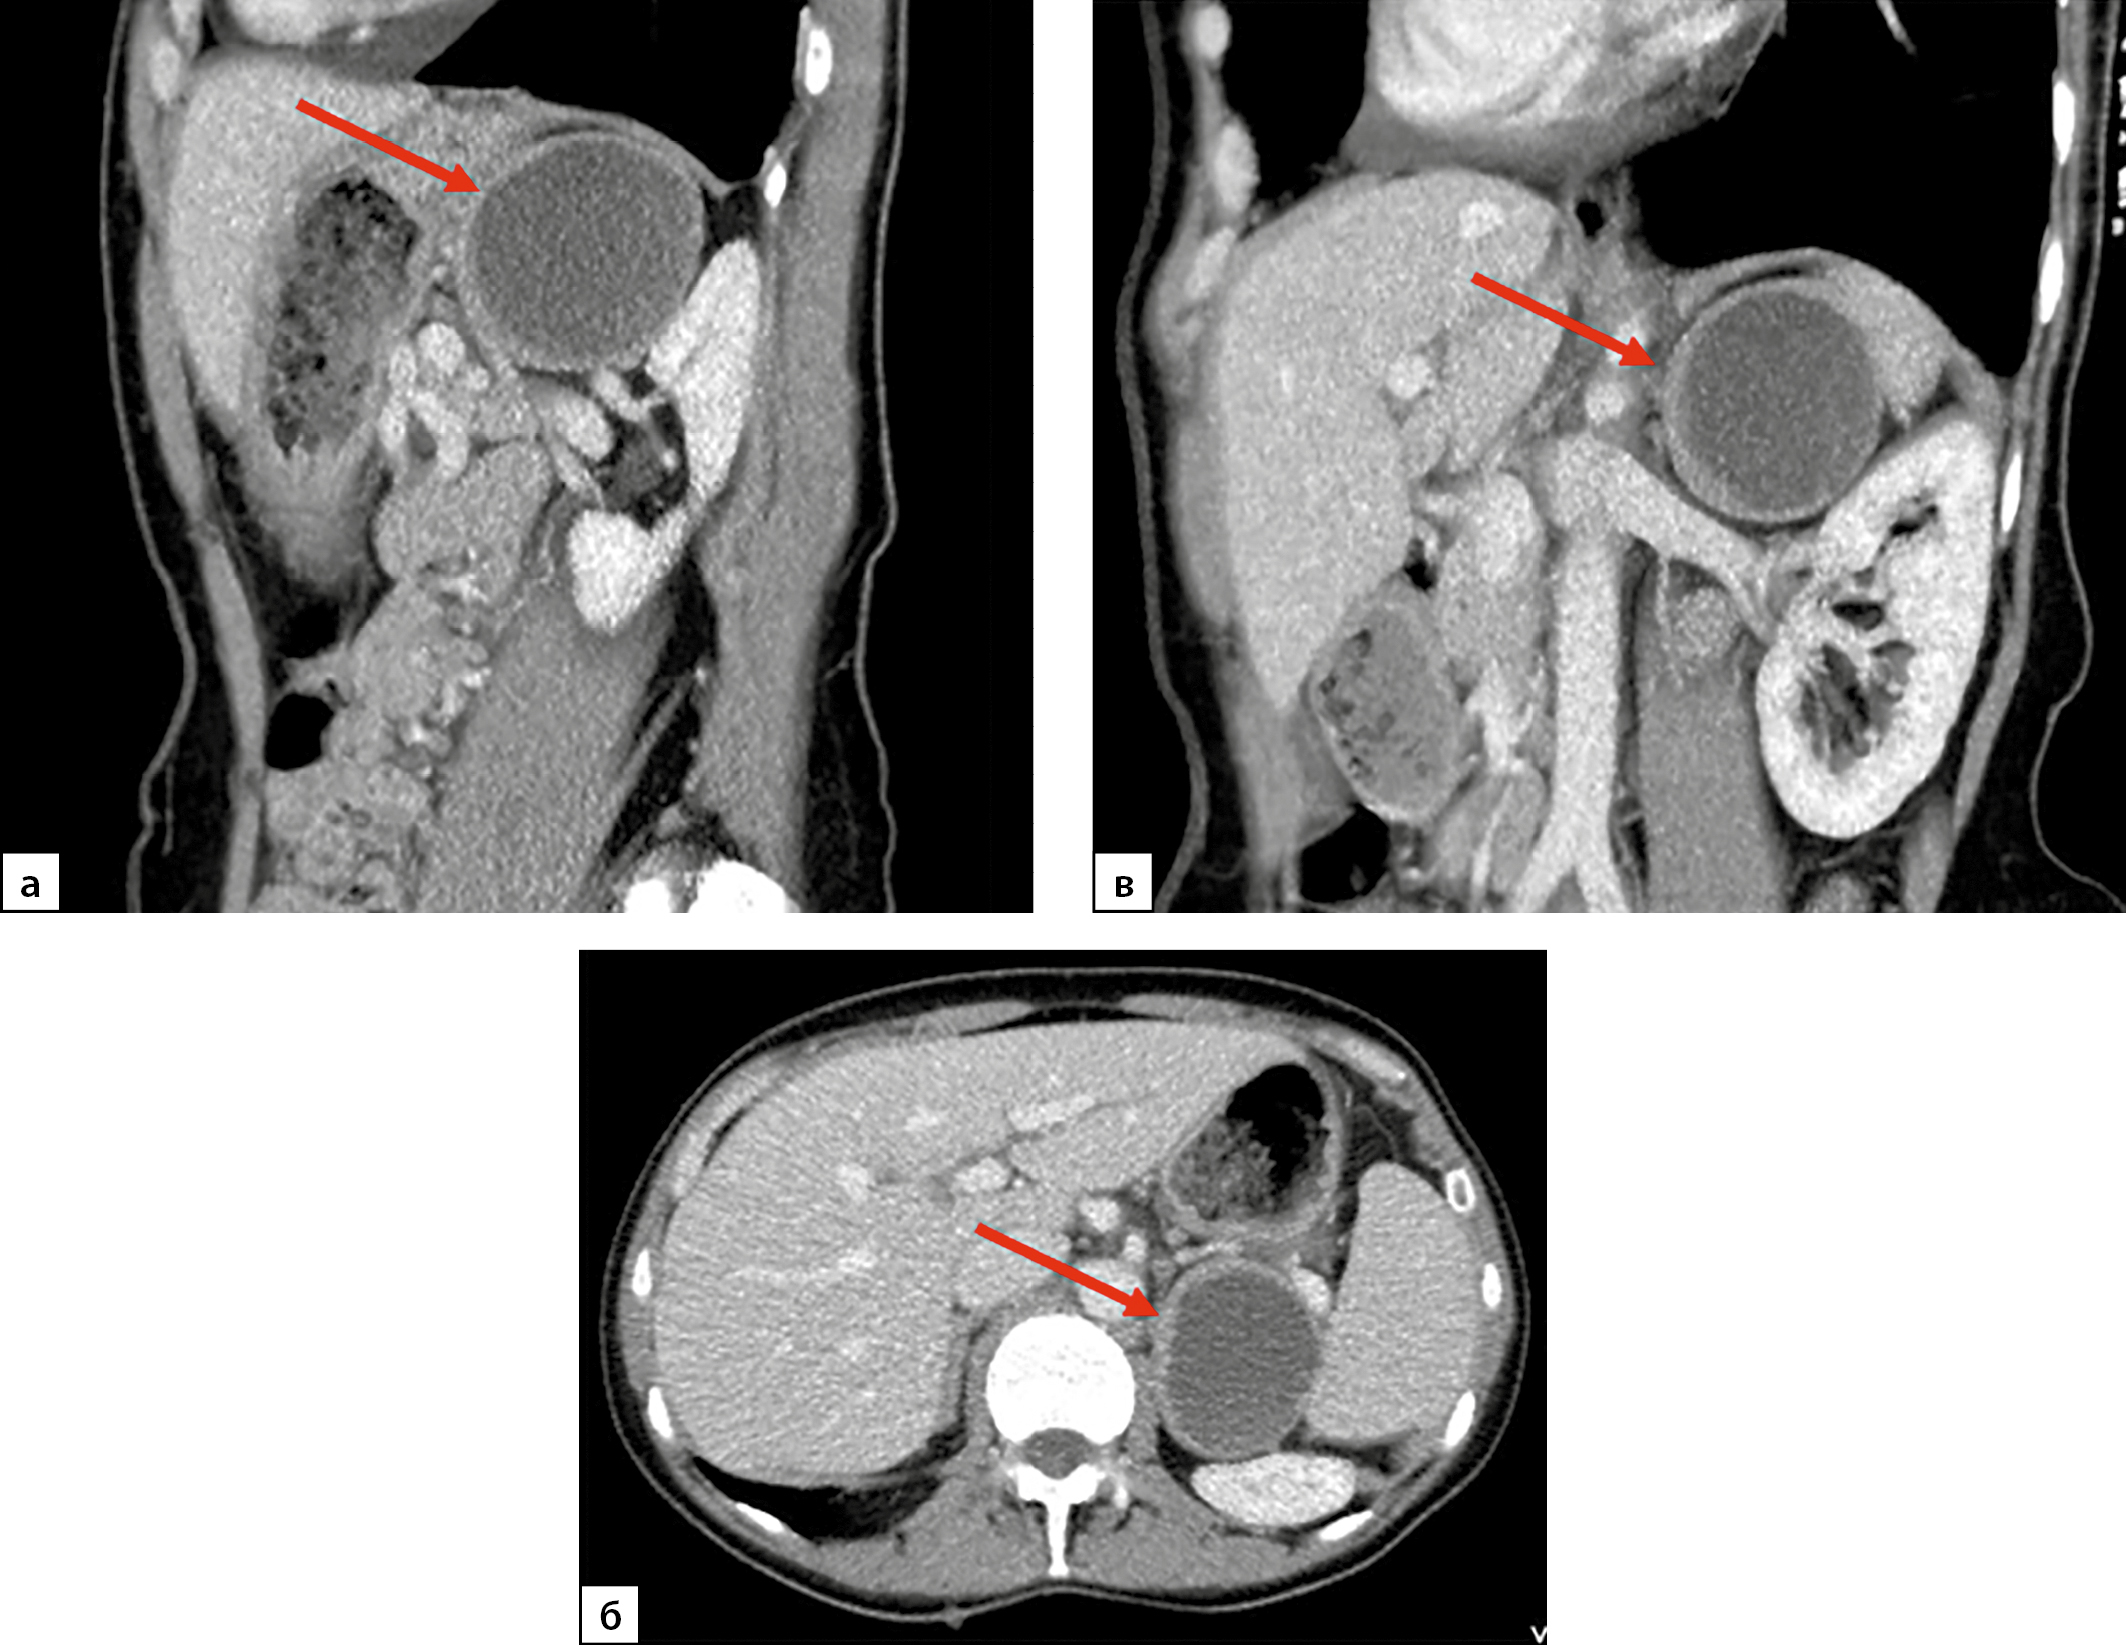

Рисунок 2. Компьютерная томография надпочечников пациентки Н., 58 лет, артериальная фаза.

а — сагиттальная плоскость, б — аксиальная плоскость, в — фронтальная плоскость. Стрелками обозначена феохромоцитома левого надпочечника, хорошо визуализируется симптом «кольцевого ободка».

По семейным обстоятельствам госпитализация с целью оперативного лечения была выполнена только через 7 месяцев после установления диагноза ФХЦ. При контроле КТ выявлено увеличение новообразования левого надпочечника в размерах до 61х49х53 мм, с кистовидной толстостенной структурой, с толщиной капсулы 3–5 мм, плотностью ткани капсулы +30 HU, накоплением контрастного вещества (КВ) максимально до +55 HU, выведением через 10 минут до +45 HU (рис. 2). На фоне целевого уровня 25ОН-витамина D 36,76 нг/мл (30–100) отмечена нормализация уровня паратгормона — 38,44 пг/мл (15–65), нормокальциемия. При суточном мониторировании электрокардиографии (ЭКГ) по Холтеру выявлена желудочковая экстрасистолия I градация по Ryan.